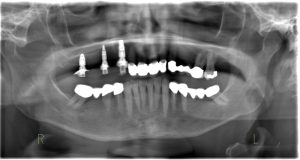

O diagnóstico padrão com escaneamento intraoral e CTCB (Fig. 3 escaner intraoral e Fig. 4 CTCB) mostrou disponibilidade óssea reduzida nas regiões 15 a 17, mas suficiente para a colocação imediata do implante. O dente 13, restaurado endodonticamente, apresentava uma obturação radicular que se estendia claramente além do ápice, juntamente com periodontite periapical. Em consulta com o paciente, foi decidido remover o dente.

O planejamento digital das posições ideais dos implantes em 3D, tanto do ponto de vista cirúrgico quanto protético, foi realizado usando o software de planejamento de implantes exoplan (exocad), com base em dados escaneados de CTCB e intraorais. O desafio era planejar a colocação imediata do implante na região 13 ao lado de dois implantes adicionais, garantindo a utilização ideal do osso disponível em termos de estabilidade primária suficiente para carga imediata por meio de uma restauração imediata provisória de longo prazo com uma ponte implantossuportada. Um implante (comprimento 10 mm, diâmetro 3,3 mm) foi posicionado exatamente na frente do seio maxilar na região 15 e o segundo implante (comprimento 8 mm, diâmetro 4,1 mm) foi planejado na região 17 (Fig. 6). As atenções do software e as indicações de distância de segurança foram particularmente úteis nesse processo.

O dente canino, considerado não restaurável, deveria ser extraído e um implante (comprimento de 12 mm, largura de 4,1 mm) colocado um implante imediatamente na região do dente 13. Uma guia cirúrgica implantossuportada foi projetada no exoplan / Guide Creator (Fig. 7) para garantir a colocação precisa do implante durante a cirurgia. Dado o planejamento da colocação imediata do implante após a extração do dente 13 e a restauração imediata, foram escolhidos implantes cônicos ao nível do osso com um design de rosca de implante agressivo (SL Active, Straumann Group) para alcançar a alta estabilidade primária necessária. Após o planejamento, a restauração provisória de longo prazo foi projetada no DentalCAD usando o Immediate Load (Fig. 8).